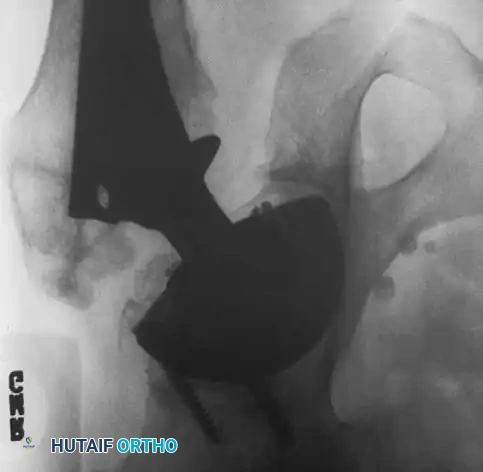

Associated Surgical & Radiographic Imaging